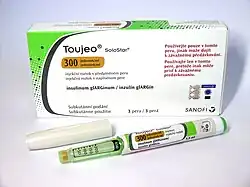

| Toujeo | Sanofi | Pen |

|

[161][162] |